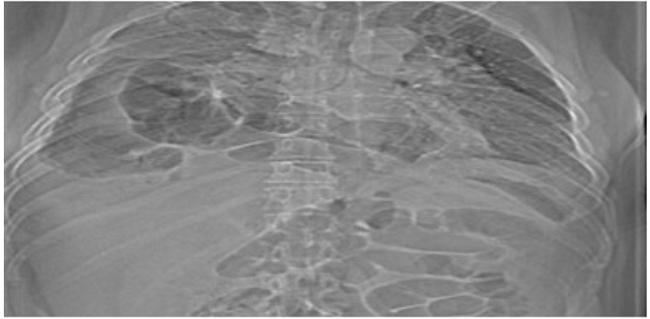

Al paciente se le realizó una radiografía de tórax PA, visualizándose unas imágenes aéreas en hemitórax derecho que comunican con el abdomen, con el aspecto de vísceras abdominales (Figura 1).

Respecto al estudio por imágenes, las hernias hiatales gigantes con estómago intratorácico pueden manifestarse como masas mediastínicas incidentales en la radiografía de tórax, donde se ven proyectadas por detrás del corazón, en el mediastino posterior, muchas veces con un nivel hidroaéreo, en el caso se encontró la presencia de imágenes aéreas en el hemitórax derecho que correspondían con el estómago y colon transverso.